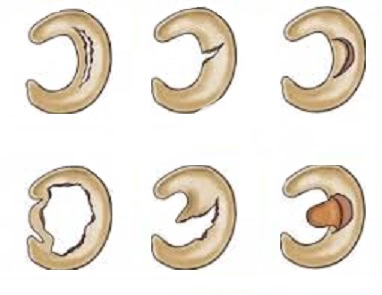

Οι ρήξεις μηνίσκου ταξινομούνται ανάλογα με τη μορφολογία τους και την εντόπιση τους στη μάζα του μηνίσκου (εικόνα 2).

σχεδόν πιστοποιούν το πρόβλημα. Σχεδόν πάντοτε, θα ζητηθεί η διενέργεια μαγνητικής τομογραφίας γόνατος η οποία θα περιγράψει με λεπτομέρεια τη ρήξη και τις πιθανές συνοδές κακώσεις (εικόνα 4 . Η εκτίμηση της θέσης και έκτασης της βλάβης είναι πολύ σημαντική για τη θεραπεία, καθώς περιφερικές ρήξεις (δηλαδή στην εξωτερική πλευρά του μηνίσκου) χωρίς επέκταση στην ελεύθερη επιφάνειά του, άνω ή κάτω, έχουν δυναμικό ίασης λόγω της επαρκούς αιμάτωσης αυτής της ζώνης.

Αντίθετα, όσο η βλάβη «προχωρά» προς τα χείλη (δηλαδή το εσωτερικό του μηνίσκου) και ιδίως αν είναι πολύπλοκης μορφολογίας, μειώνονται σημαντικά οι πιθανότητες συντηρητικής θεραπείας. Το ίδιο ισχύει και στις περιπτώσεις που η ρήξη περιγράφεται ως «επεκτεινόμενη στην αρθρική επιφάνεια του μηνίσκου». Βεβαίως στη φάση αυτή ο θεράπων γιατρός θα συζητήσει με τον ασθενή και άλλους παράγοντες, όπως ηλικία, δραστηριότητα, ώστε να λάβει την ορθή θεραπευτική απόφαση. Είναι σύνηθες φαινόμενο οι ασθενείς να λαμβάνουν συχνά διαφορετική συμβουλή για το πότε κάνουμε αρθροσκόπηση και πότε όχι. Επίσης, λαμβάνουν συχνά διαφορετική εκτίμηση για την ανάρρωση μετά από αρθροσκόπηση. Άλλωστε μια μικρή «βόλτα» στα φόρουμ αρθροσκόπησης γόνατου αρκεί για να διαπιστώσει κάποιος την ανησυχία του κόσμου για το πότε κάνουμε αρθροσκόπηση, την αποτυχία της αρθροσκόπησης, το κόστος της στον ιδιωτικό τομέα ή σε ένα δημόσιο νοσοκομείο πχ αρθροσκόπηση στο Metropolitan ή αρθροσκόπηση στο νοσοκομείο ΚΑΤ?